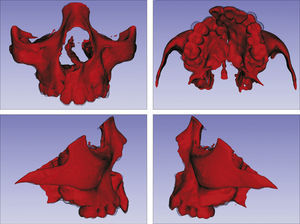

O surgimento e o aumento da acessibilidade da TCFC agregaram uma maior credibilidade ao diagnóstico clínico e às investigações científicas no estudo das deformidades craniofaciais19. Todavia, as informações 3D fornecidas pelas TCFC ainda vêm sendo rotineiramente analisadas de forma 2D, por medidas lineares em cortes ortogonais5,20. A construção e sobreposição de modelos virtuais 3D ainda é uma metodologia pouco difundida. Este estudo é um dos pioneiros que utiliza este método para avaliação de ERM em pacientes com fenda. A sobreposição baseia‐se na construção dos modelos virtuais 3D, utilizando o software SLICER21, pelos arquivos obtidos na TCFC, seguida pela sua justaposição, que utiliza a base do crânio como referência e a final obtenção dos métodos de medidas intitulados: sobreposição por semitransparência e mapa por códigos de cores22. A sobreposição por semitransparência revela uma análise qualitativa, em que o momento pós‐tratamento é retratado por uma malha preta translúcida, sobre o modelo inicial em vermelho (figs. 9 e 10). O aparelho em leque demonstrou um deslocamento de quase todos os dentes para vestibular e uma movimentação vestíbulo‐posterior do segmento menor (lado esquerdo [fig. 9]). O mapa por códigos de cores permite um complemento da análise visual, sendo que cada cor reflete uma alteração na posição das estruturas: azul – recuo; verde – estabilidade e vermelho – expansão. A intensidade da cor está diretamente relacionada à quantidade de movimentação. Todo o mapa é seguido por uma escala, com os valores em milímetros para cada cor (figs. 11 e 12). A observação feita na sobreposição por semitransparência do expansor em leque é confirmada no mapa por código de cores e nas medidas lineares. Uma menor porção de vermelho é visualizada em molares, quando comparada aos pré‐molares. O deslocamento para posterior e vestibular do menor segmento é constatado pela presença de azul na mesial dos dentes e vermelho nas eminências alveolares do lado em questão. Diferentes tonalidades de azul são vistas na cervical dos incisivos, possivelmente uma retroinclinação em decorrência da ausência de apoio mecânico no local. Para a quantificação das mudanças no posicionamento dentário, primeiramente identificou‐se, nos 3 cortes ortogonais, os pontos de referência para a medida (ponta da cúspide mésio vestibular dos primeiros molares superiores e ponta da cúspide dos caninos), tanto do lado direito como do lado esquerdo, utilizando o software ITK Snap23. Os pontos foram marcados com uma esfera de 0,5mm de diâmetro, identificando a posição 3D destas referências no espaço (fig. 13). A aferição das distâncias Euclidianas entre as esferas foi realizada com o auxílio da ferramenta Q3DC no programa SLICER23. O paciente A obteve um aumento de 3mm na distância intercanina e de 6mm na distância intermolar. Na elucidação do paciente que utilizou o disjuntor mini‐Hyrax invertido com BTP (B), observa‐se na sobreposição por semitransparência um deslocamento vestibular, principalmente dos pré‐molares e uma constância das demais áreas, achados corroborados no mapa por código de cores. A área que não está verde é a região de pré‐molares, vermelho por vestibular e azul por palatino, notando uma tonalidade entre verde e vermelho (amarelo) no corpo da maxila do lado menor (esquerdo). A oclusal dos molares, em vermelho, representa a erupção dos elementos.

Sobreposição com semitransparência dos modelos 3D do tratamento com o aparelho mini‐Hyrax invertido com BTP. Antes da expansão representado por vermelho e após a expansão pela malha fina translúcida. Observa‐se um trespasse da malha preta para vestibular na região dos pré‐molares, indicando expansão concentrada nessa região.